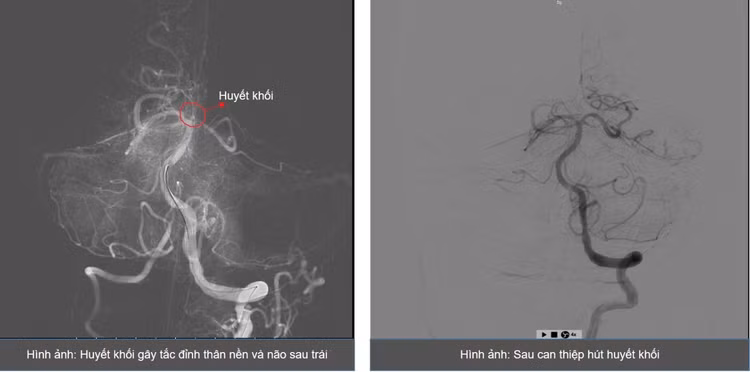

ThS.BS Giáp Hùng Mạnh – Trưởng khoa Thần kinh, Vật lý trị liệu – Phục hồi chức năng, Bệnh viện Bãi Cháy cùng ê-kíp đã tiến hành chụp mạch não, phát hiện tắc gốc động mạch đốt sống trái, trong khi động mạch đốt sống phải có kích thước nhỏ.

Ê-kíp quyết định hút huyết khối tại vị trí tắc, tái lập một phần dòng máu lưu thông nhưng phát hiện hẹp nặng gốc động mạch đốt sống trái. Các bác sĩ tiếp tục nong bóng và đưa ống hút chuyên dụng qua vị trí hẹp.

Sau can thiệp, hình ảnh chụp mạch cho thấy tắc động mạch đốt sống đoạn trên và thân nền. Ê-kíp tiếp tục hút huyết khối và bơm thuốc tiêu sợi huyết tại chỗ. Sau khoảng 10 phút, chụp kiểm tra cho thấy mạch máu được tái thông hoàn toàn.

Theo ThS.BS Giáp Hùng Mạnh, đây là trường hợp khó do có hẹp rất nặng gốc động mạch đốt sống và tắc mạch ở nhiều vị trí, đặc biệt là ở vị trí đỉnh của động mạch thân nền – động mạch cấp máu cho các cấu trúc sống còn của hệ thần kinh trung ương.